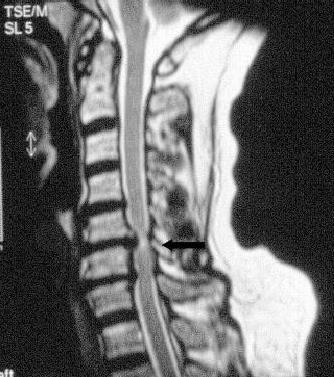

Usually it is enough to organize a nuclear resonance imaging for diagnosing a stenosis at the region of the cervical spine. If there is the suspicion that the spinal cord has been damaged it is necessary to perform an electropysiological examination to ensure the conductivity of the nerves.